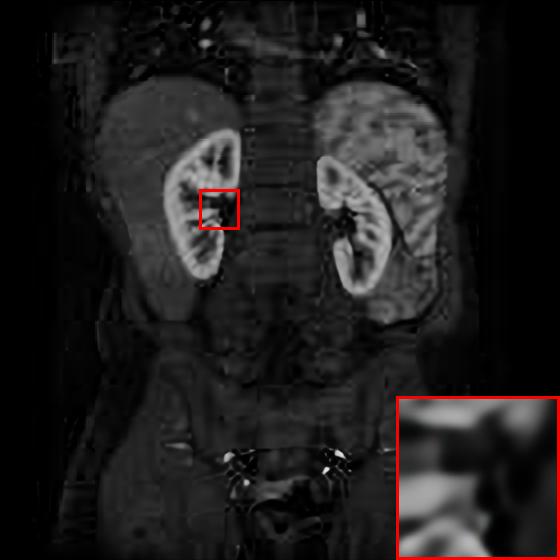

Figure 4: Reconstruction results of each algorithm for abdominal MRI images.

The PNSR/SSIM test results for the knee MRI test images for all contrast methods are shown in Table 1. The PNSR/SSIM test results for the abdominal MRI images are shown in Table 2. It’s worth noting that all metrics were calculated on cropped photos in order to eliminate the impact of non-subject areas. The quantitative results show that for knee MRI images, our proposed TT\mathrm{T}-GAN model achieves the best performance on the PSNR/SSIM metrics. For abdominal MRI images, our model essentially achieves optimal performance, with individual image WDSR slightly outperforming our model. The experimental results cousin that our model is more suitable for medical image super-resolution reconstruction than the existing deep learning-based image super-segmentation models.

We likewise give the visualization comparison results for each comparison algorithm, as shown in Fig. 3 and Fig. 4. It can be seen that the reconstructed images based on bicubic interpolation and deep learning based EDSR and WDSR both show oversmoothing phenomenon and some loss of detail information of the images. In contrast, our T-GAN performs better for the reconstruction of detail information due to the texture Transformer structure.